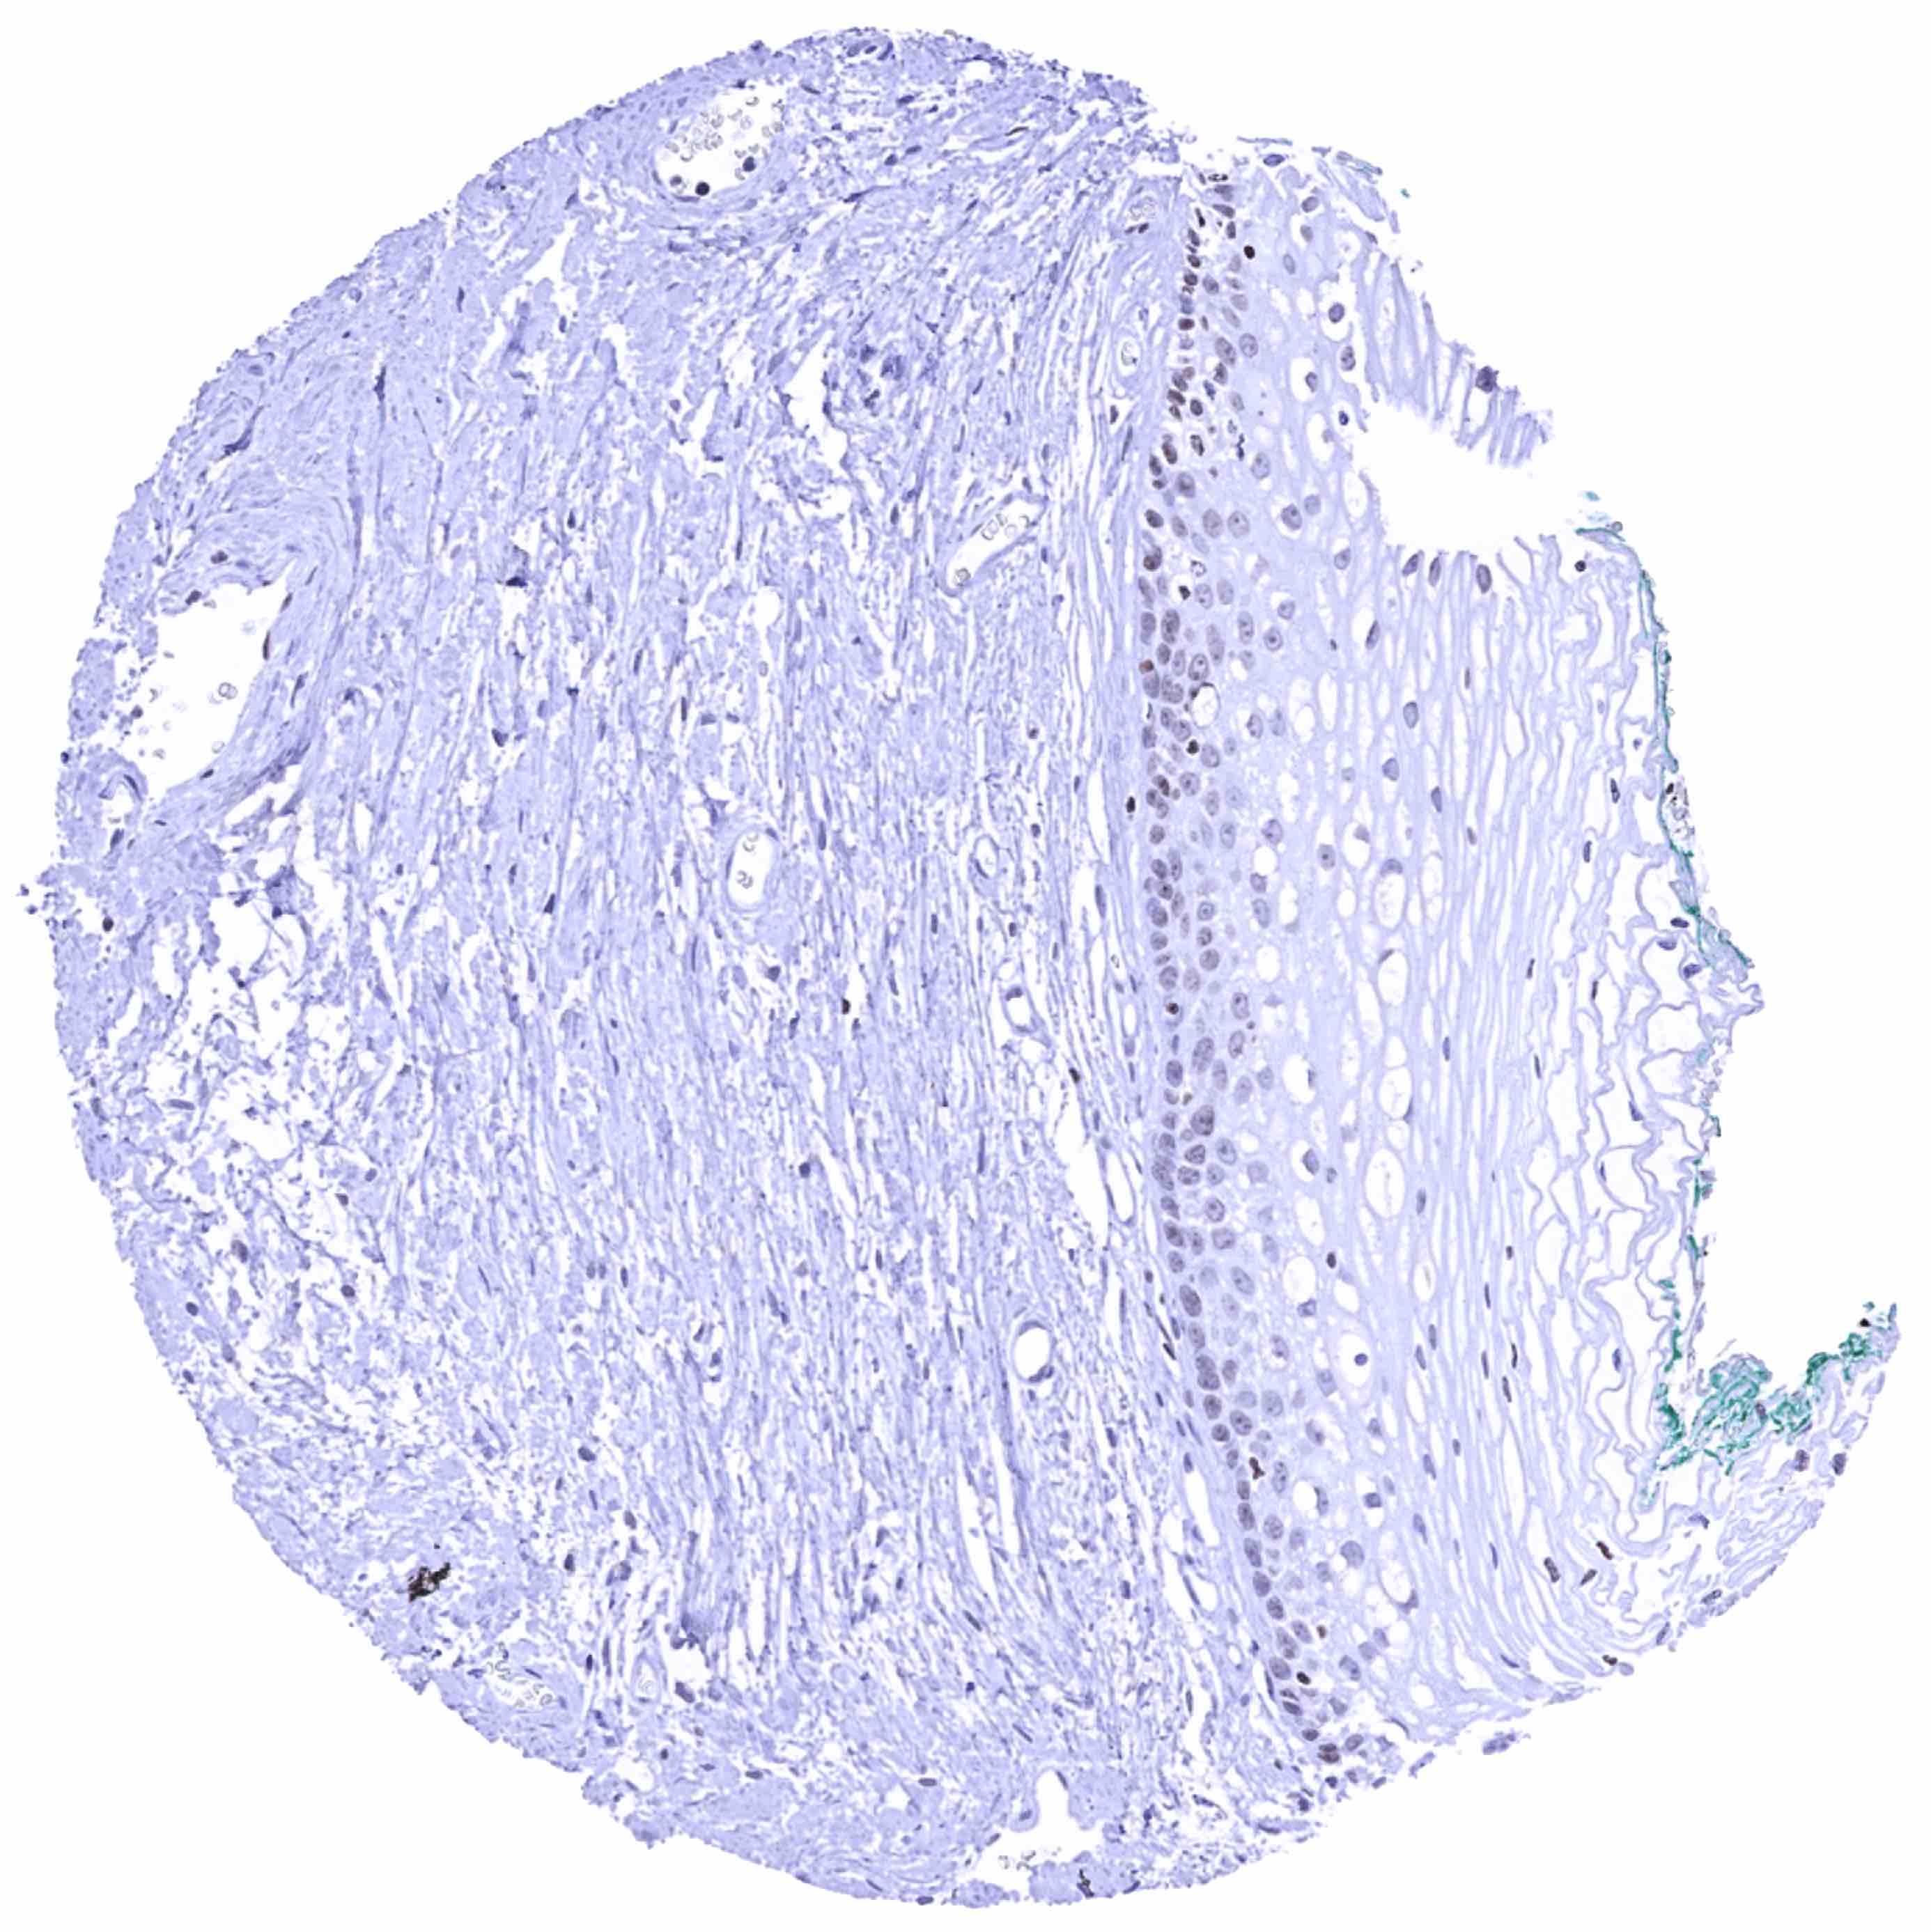

Urinary bladder, urothelium – Few urothelial cells show a weak nuclear HMGA2 positivity

Uterus, ectocervix

Uterus, endocervix – Strong nuclear HMGA2 staining of epithelial cells